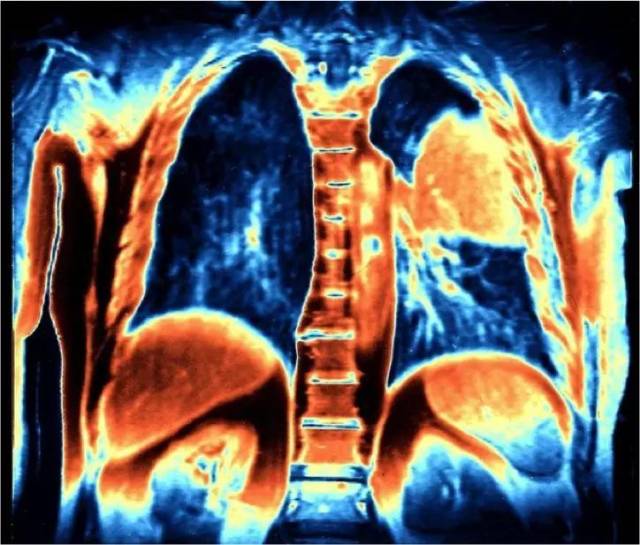

彩色磁共振成像扫描右上方橙色肺部恶性肿瘤, 单纯化疗已不再是肺癌的